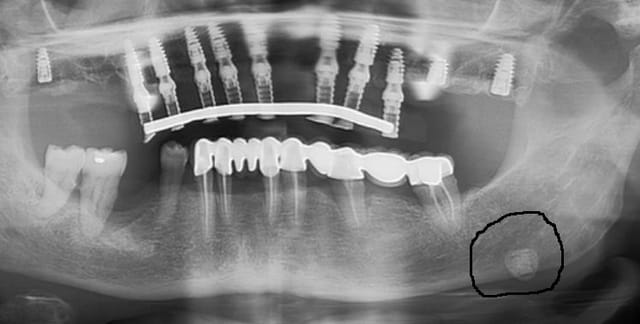

Je soumets un cas à vos critiques ( la prothèse d'usage ne remplacera pas les deuxièmes molaires car la patiente refuse les greffes )

je demande l'avis de gens ayant l'expérience de ce genre de cas. Mon associé, par exemple trouve que je mets trop d'implant. Je ne fais pas d'extension en haut d'où les implants postérieurs qui seront reliés par une poutre, on me dit que c'est inutile etc ...

je voulais donc juste savoir comment vous auriez traité ce cas

Joli boulot, as-tu utilisé un guide ?

Quelle est ta technique de MCI ?

Vu le manque d'hygiène de la patiente, j'espère que tu l'as bien briefé :) Le bas est prévu pour quand ?

Edit : en effet les deux implants postérieurs ne servent à mon avis à rien.

Question annexe : c'est quoi ce truc ?

Capture vigkq1 - Eugenol

je ne sais pas, la patiente doit voir un stomato

j'avais fait une gouttière à partir du modèle d'étude avec une plaque un peu rigide pour me faire un guide chir.

ça fait deux mois que je la suis et tente d'améliorer son hygiene ( h2o2 + bicar), diminution du tabac , détartrage.

je pensais que les implants postérieurs renforçaient le bridge, bon, je le saurai pour la prochaine fois !

Ca fait pas de mal, hein, c'est pas ça que je veux dire, c'est que tu te dois, toutes choses étant égales par ailleurs, de proposer à ton patient le traitement le plus léger possible (tant au niveau de la chirurgie, qu'au niveau financier).

Tu aurais eu le même résultat sans ces implants, étant donné que tu ne remplaces pas les 7.

La localisation de cette radio-opacite et sa tonalité font penser a une lithiase de la glande sous mandibulaire ( à confirmer par l anamnèse et la palpation). Ça peut être aussi une calcification d un lympho noeud

Ils serviront à quoi les implants en 18, 26, 28?

je m'en sers d'appuis pour renforcer le système, je n'aime pas trop les extensions.

Les "tout sur 6" fonctionnent très bien avec des extensions raisonnables. 5-8 mm. Perso, je penses que tu sécurise plus ton esprit que le patient. Prothèse plus complexe, contrôle de plaque hyper compliquée, coût très augmenté, je suis pas du tout convaincu mais tu ne fais pas d'erreur et personne ne peut te reprocher ton choix.

Quand je peux en mettre 8 et que le patient accepte le prix , je préfère toujours 8... Plus de sécurité, hygiène plus facile et confort meilleur car moins de pontiques mais l'implant postérieur est souvent problématique, donc ce ne sera jamais mon choix de les placer aussi loin sauf éventuellement si le dernier implant se trouve en canine- 1ère prémolaire je me poserai éventuellement la question.